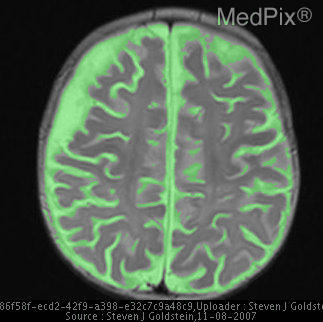

Refer to caption

Figure 1: Overview of MedVistaGym, which contains a comprehensive suite of reasoning-intensive medical image analysis tasks and tools in an interactive execution environment, scaling visual-centric tool-integrated agentic reinforcement learning for VLM agents.